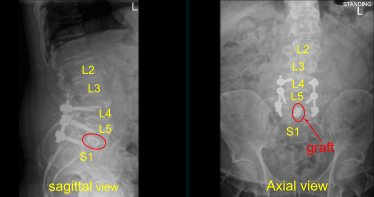

Case Study: L4-S1 Posterior Instrumented Fusion with L5-S1 Transforaminal Lumbar Interbody fusion with Osteotomy

The patient presented to outpatient clinic status post motor vehicle accident with signs and symptoms of lumbosacral spondylolisthesis, bilateral L5 spondylolysis, L5 compression fracture, severe compression of L5 nerve root, and clinically with foot drop, severe radiculopathy and back pain. Surgery was recommended to decompress and stabilize the lumbosacral spine.

Nerve root retractor was used to retract thecal sac and S1 nerve root medially towards the patient’s right side. Due to the spondylolisthesis and collapse, which appeared to be worse on the CT scan with bone-on-bone. We had to perform resection of sacral promontory on the left side exposing with Bovie using Kerrison rongeurs and osteotomy to pass through the posteroinferiorly corner of the L5 body, which was collapsed on the sacral endplates.